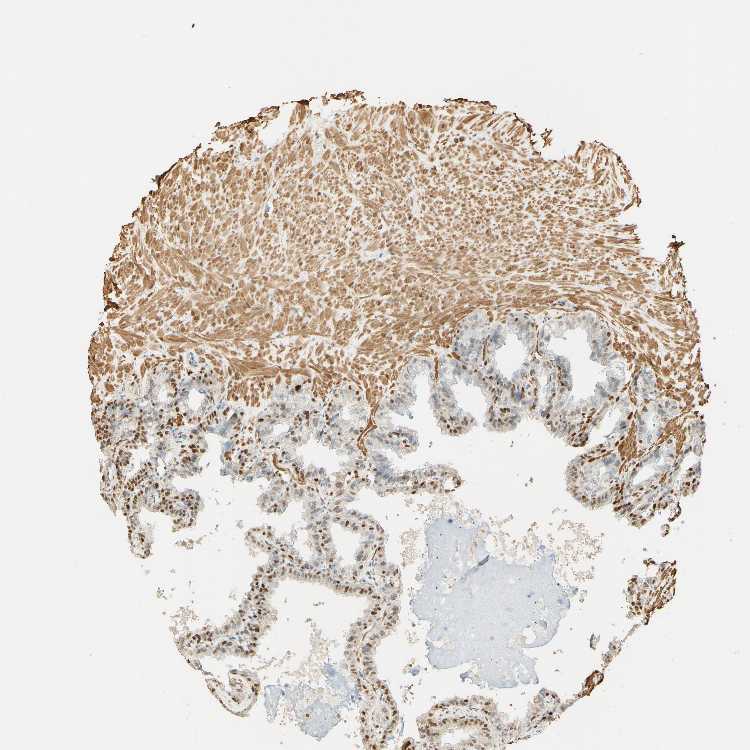

SEMINAL VESICLE - Antibody stainingi

Antibody staining in the annotated cell types in the current human tissue is reported as not detected, low, medium, or high, based on conventional immunohistochemistry profiling in selected tissues. This score is based on the combination of the staining intensity and fraction of stained cells.

Each image is clickable and will lead to virtual microscopy that enables deeper exploration of all samples and also displays staining intensity scores, fraction scores and subcellular localization as well as patient and tissue information for each sample.

Antibody HPA007625

Glandular cells High